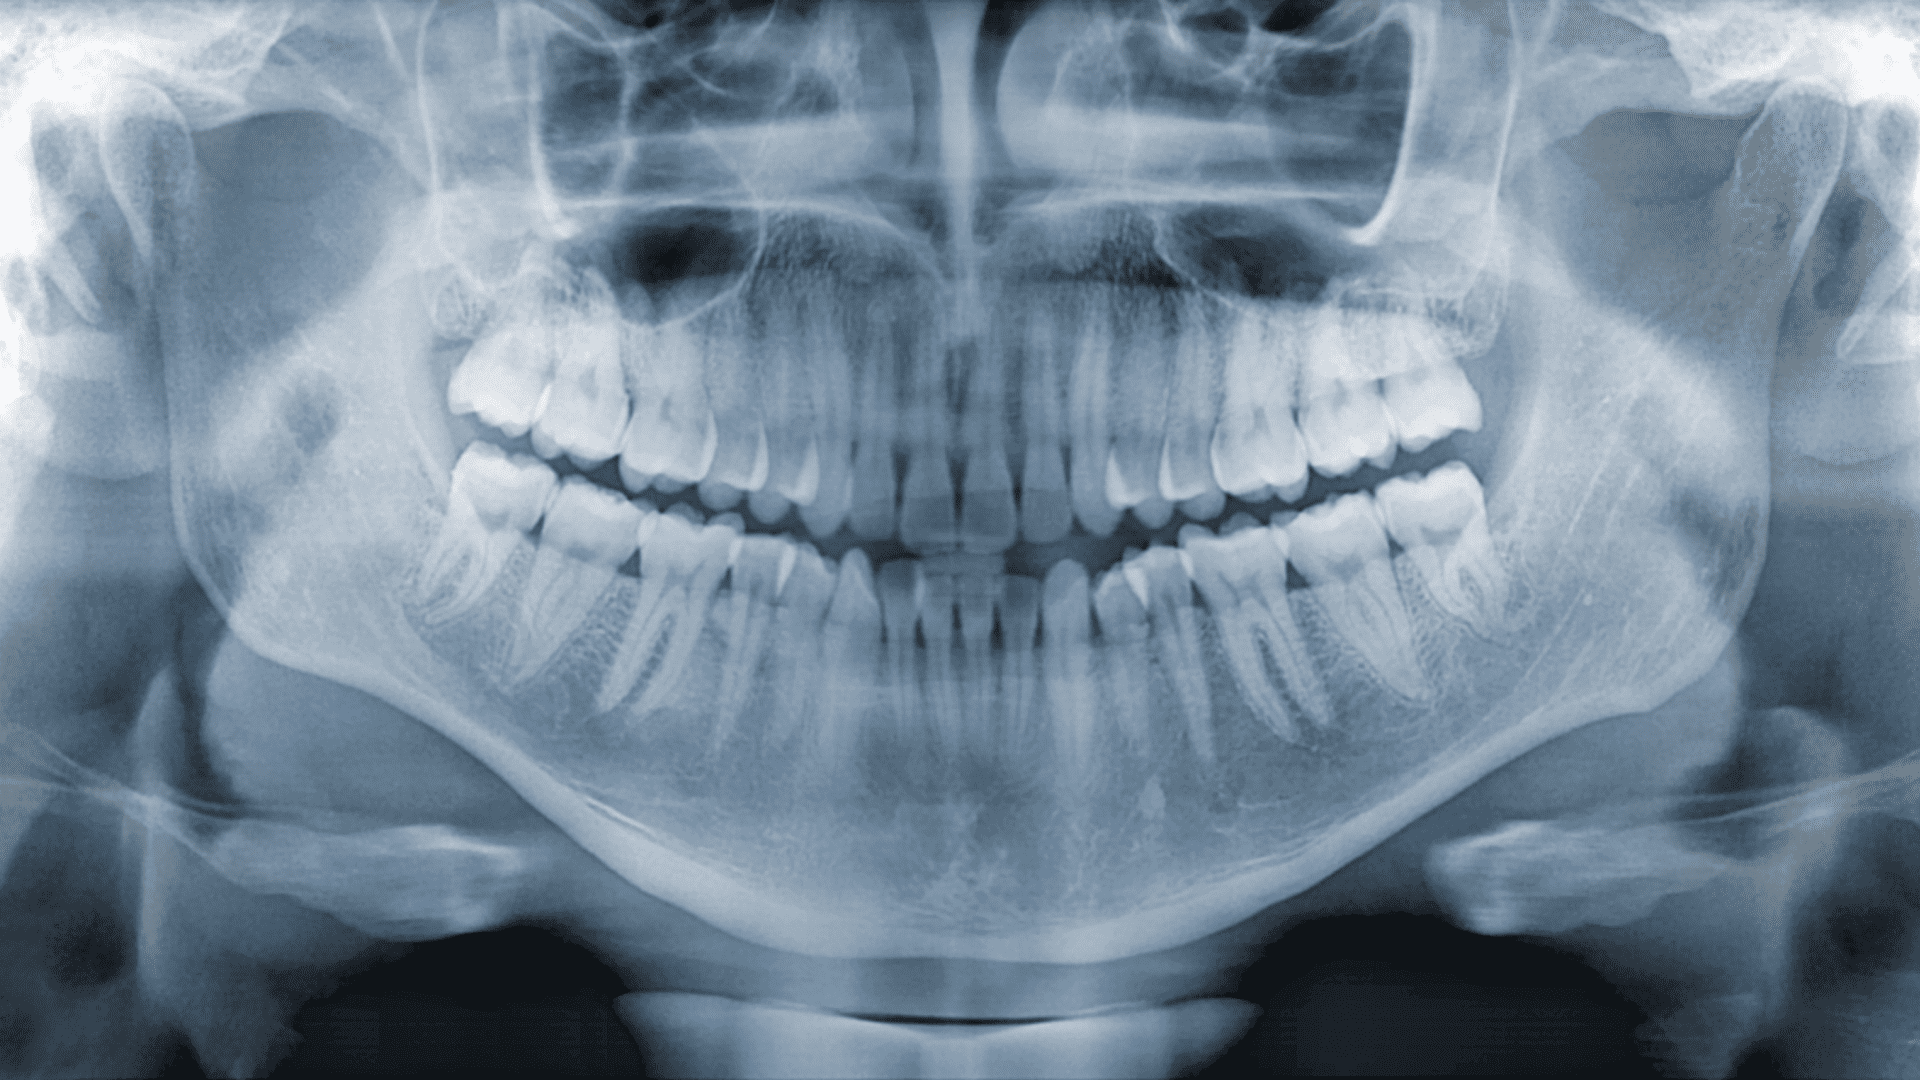

Підготовка до імплантації передбачає проведення серії рентгенологічних досліджень. Залежно від конкретного випадку пацієнту призначають одну або кілька нижченаведених видів рентгенографії:

• прицільний (або локальний) знімок проводиться за відсутності одного зуба;

• панорамний знімок (ортопантомограма) – за відсутності одного, двох або трьох зубів;

• комп’ютерна томографія – за відсутності будь-якої кількості зубних елементів.

• Чи обов’язково робити комп’ютерну томографію перед імплантацією?

Сучасна імплантація передбачає обов’язкове проведення КТ. Пов’язано це із плануванням операції. Лікар має врахувати найдрібніші деталі та фактори, інформацію про які він може дізнатися з даних по КТ. Якщо обмежитися лише рентгенографічними знімками, підвищується ймовірність помилок при імплантації.

• Підготовка до імплантації передбачає проведення рентгенологічного дослідження та комп’ютерної томографії (КТ). Остання необхідна для грамотного моделювання процесу імплантації.